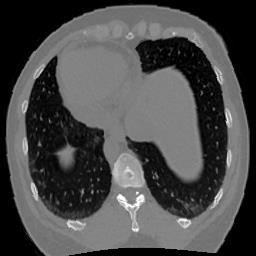

In clinical practice, well-aligned multi-modal images, such as Magnetic Resonance (MR) and Computed Tomography (CT), together can provide complementary information for image-guided therapies. Multi-modal image registration is essential for the accurate alignment of these multi-modal images. However, it remains a very challenging task due to complicated and unknown spatial correspondence between different modalities. In this paper, we propose a novel translation-based unsupervised deformable image registration approach to convert the multi-modal registration problem to a mono-modal one. Specifically, our approach incorporates a discriminator-free translation network to facilitate the training of the registration network and a patchwise contrastive loss to encourage the translation network to preserve object shapes. Furthermore, we propose to replace an adversarial loss, that is widely used in previous multi-modal image registration methods, with a pixel loss in order to integrate the output of translation into the target modality. This leads to an unsupervised method requiring no ground-truth deformation or pairs of aligned images for training. We evaluate four variants of our approach on the public Learn2Reg 2021 datasets \cite{hering2021learn2reg}. The experimental results demonstrate that the proposed architecture achieves state-of-the-art performance. Our code is available at https://github.com/heyblackC/DFMIR.